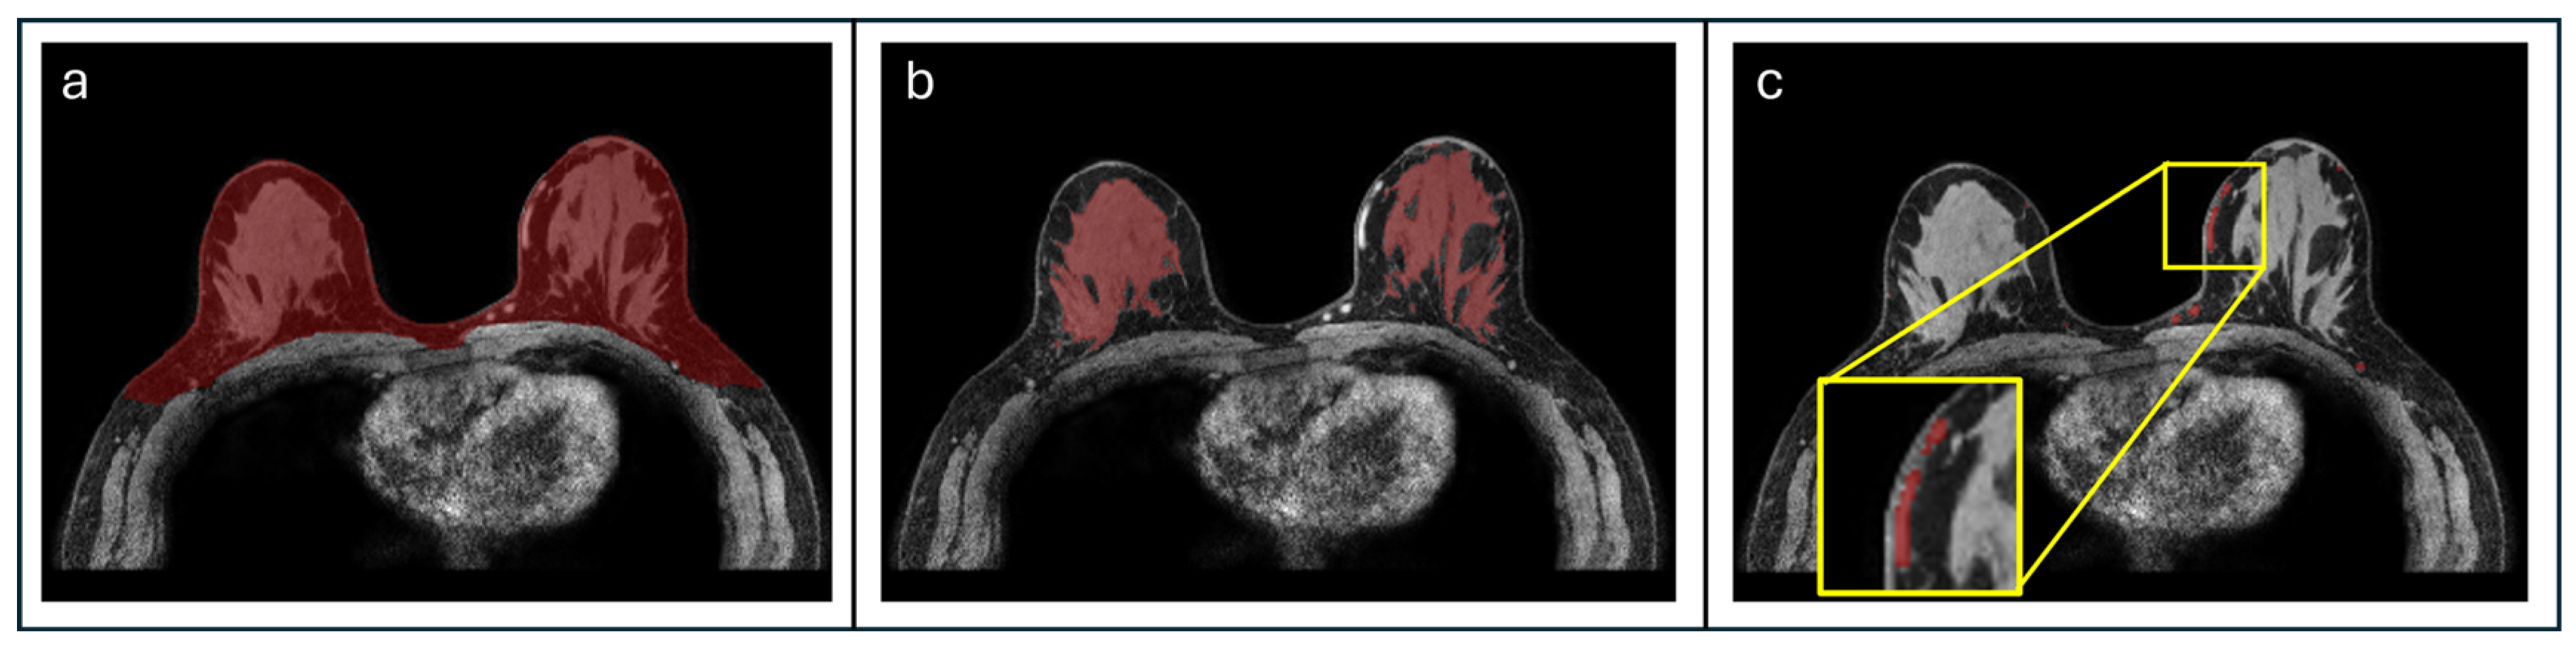

- Lew, C.O.; Harouni, M.; Kirksey, E.R.; Kang, E.J.; Dong, H.; Gu, H.; Grimm, L.J.; Walsh, R.; Lowell, D.A.; Mazurowski, M.A. A publicly available deep learning model and dataset for segmentation of breast, fibroglandular tissue, and vessels in breast MRI. Sci. Rep. 2024, 14, 5383. [Google Scholar] [CrossRef]

- Kuo, Y.T.; Kazerouni, A.S.; Park, V.Y.; Surento, W.; Hippe, D.S.; Rahbar, H.; Partridge, S.C. Validation of Fully-Automated Deep Learning-Based Fibroglandular Tissue Segmentation for Efficient and Reliable Quantitation of Background Parenchymal Enhancement in Breast MRI. arXiv 2025, arXiv:2511.07088. [Google Scholar]